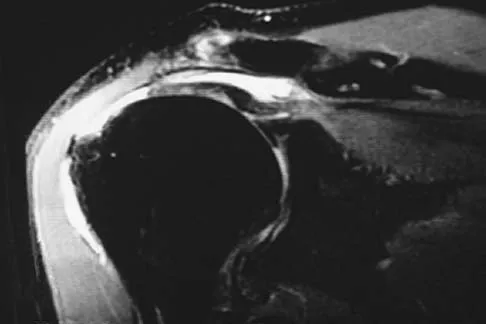

A previously asymptomatic 40-year-old man injures his shoulder in a fall. Examination shows that he is unable to lift the hand away from his back while maximally internally rotated. An axial MRI scan of the shoulder is shown in Figure 14. What is the most likely diagnosis?

Figures 36a and 36b show the MRI scans of a patient who has shoulder weakness. What is the most likely diagnosis?

A 24-year-old athlete has a painful right shoulder. Figure 30 shows an intra-articular photograph that was obtained through a posterior portal during arthroscopy; the labrum is indicated by the arrow. Based on these findings, management should consist of

A patient has right shoulder pain. Figure 1a shows a gadolinium-enhanced transverse MRI scan at the level of the coracoid. Figure 1b shows an arthroscopic view of the anterior structures from a posterior portal. These images reveal which of the following findings?

A 21-year-old patient has had pain and a marked decrease in active and passive shoulder motion after having had a seizure 2 months ago as the result of alcohol abuse. Current AP and axillary radiographs and a CT scan are shown in Figures 26a through 26c. Management should consist of